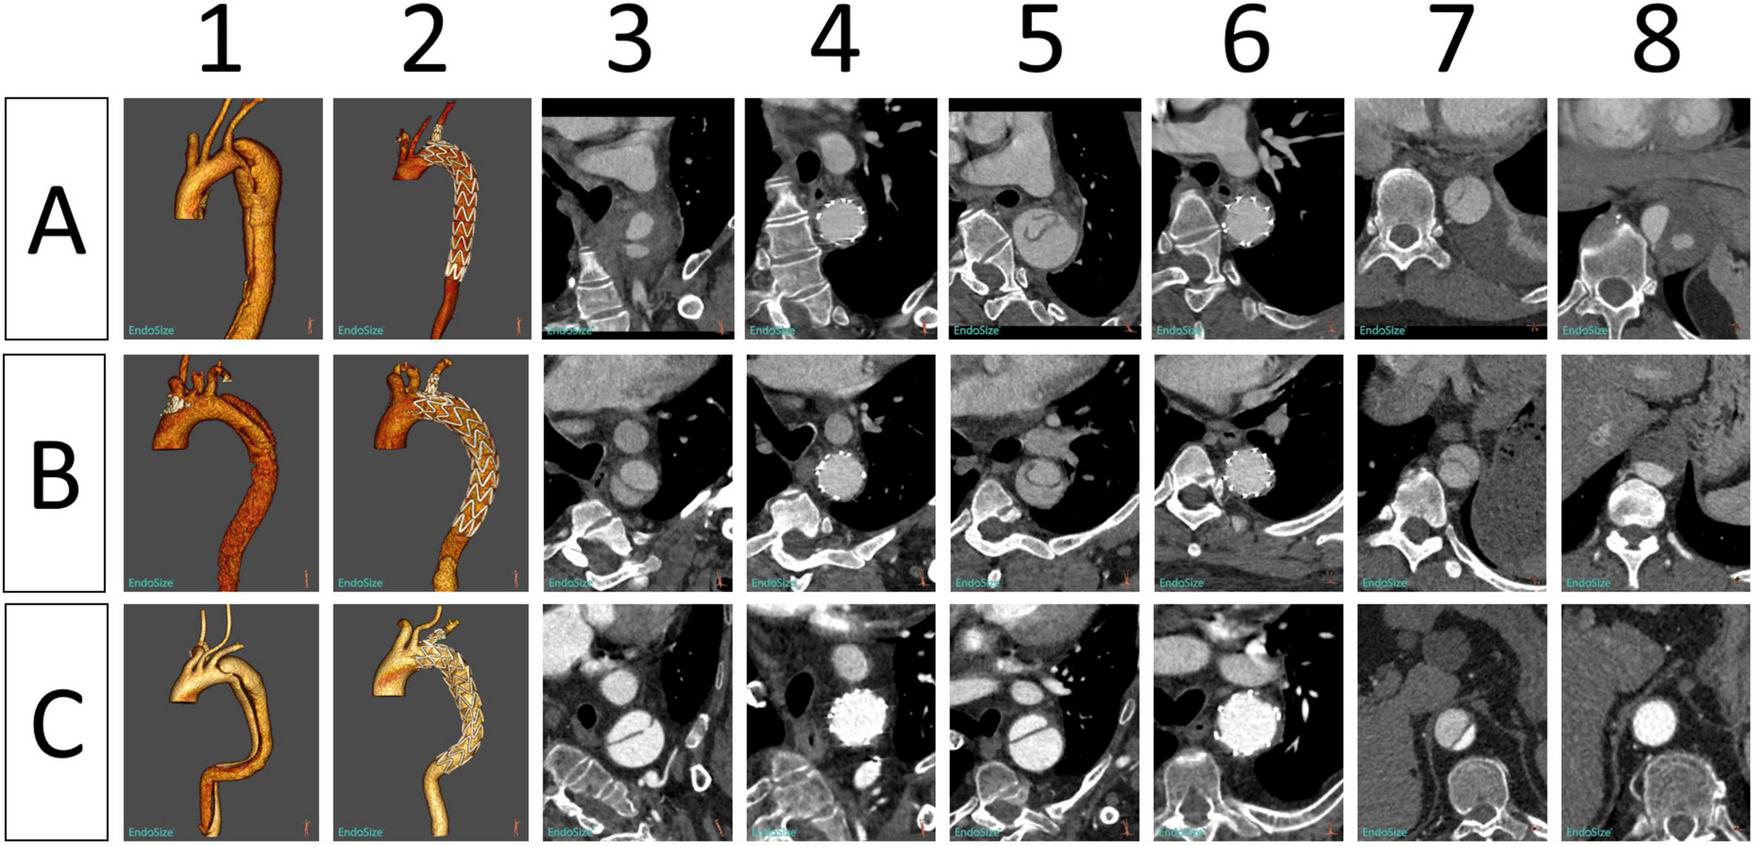

In 42 patients with AD, the last CTA examination showed complete thrombosis in the false lumen of distal aortic arch and proximal descending aorta. The rate of complete thrombosis in the aortic isthmus was 100%. Complete thrombosis in the false lumen at the level of the pulmonary artery bifurcation occurred in 39 patients, and partial thrombosis was observed in three patients. Complete and partial thrombosis at the level of the diaphragm occurred in 19 and 23 patients, respectively (Table 3). The false lumen diameter at the level of the aortic isthmus and pulmonary artery bifurcation decreased significantly (P < 0.01), whereas the true lumen diameter increased significantly (P < 0.01). Thrombosis in the distal aorta was partial because of the presence of re-entry tears. There were no significant differences in the diameter of true and false lumens at the diaphragm level between before and after the operation (P > 0.05) (Table 4 and Figure 5).

FIGURE 5

Morphological changes in the aorta in three patients (A–C) before and after implantation of Castor single-branched stent grafts. (1, 2) Preoperative and postoperative 3D reconstruction of the thoracic aorta. (3, 4) Preoperative and postoperative images of the aortic isthmus. (5, 6) Preoperative and postoperative images at the level of the pulmonary artery bifurcation. (7, 8) Preoperative and postoperative images of the aorta at the level of the diaphragm.